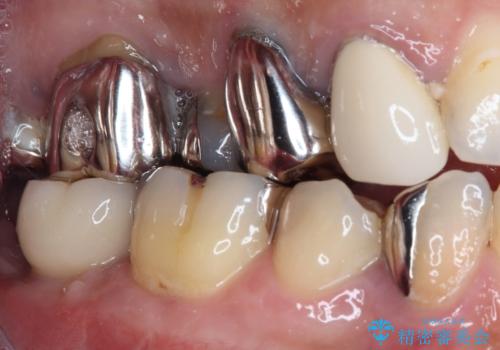

- 下顎左右の奥歯を治療途中で放置してしまっているとのことで来院された患者様です。

欠損部はインプラントによる補綴治療を、土台の外れてしまった歯は、根管治療を行った上で、補綴治療を行うこととしました。

骨格的に下顎が大きく上顎が小さいため、奥歯に力の負担のかかりやすい咬み合わせであるので、治療後は睡眠時にマウスピースを装着することで、セラミッククラウンやインプラント、治療をしたご自身の歯が長持ちするよう指導しています。